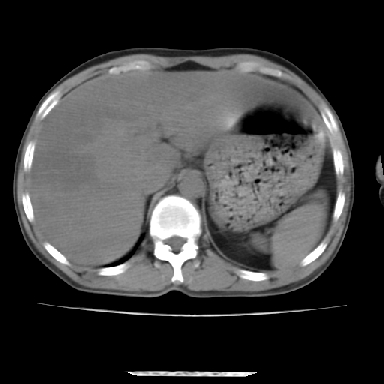

标题: CT7372:脂肪肝?外伤? [打印本页]

标题: CT7372:脂肪肝?外伤?

m 45 车祸,硬膜下血肿

窗宽太宽,调低点就好了,应该是不均质脂肪肝表现,请结合临床,单纯肝挫伤  其内无出血灶很少见,必要时做mri检查

窗宽太大,对比度太差了。局限性脂肪肝也有可能,但是亦不排除外伤性改变,增强扫描应该也还可以鉴别的。

肝内未见出血灶,但不能除外外伤性肝损伤,所示层面应考虑弥漫性脂肪肝.请结合临床必要时做mir检查

肋骨无骨折,腹腔未见游离液体,所以不均匀脂肪肝首先考虑,但如果病人情况允许还是做个增强检查放心

考虑不均匀性脂肪肝,肝包膜下光整,肋骨无异常,无腹水征,不支持肝挫伤。